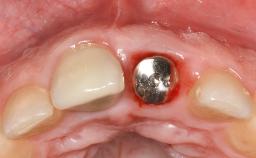

Paolo Casentini and Matteo Chiapasco present a case in which the peri-implant defect was not suitable for a fully regenerative approach. It involves implant removal, use of a CAD/CAM customized titanium mesh in the grafting phase, and placement of new implants. A 62-year-old woman was referred for consultation regarding her implant-supported prosthesis replacing teeth 14 to 16. The patient’s main concern was pain and recurrent swelling in the right posterior maxilla. The patient also reported difficulty and discomfort when brushing the area. The patient reported she had been treated in another country, where she had received three implants in combination with sinus-floor augmentation for the replacement of the posterior maxillary teeth three years earlier. The patient indicated “endodontic complications” to be the reason for the extraction of the teeth.